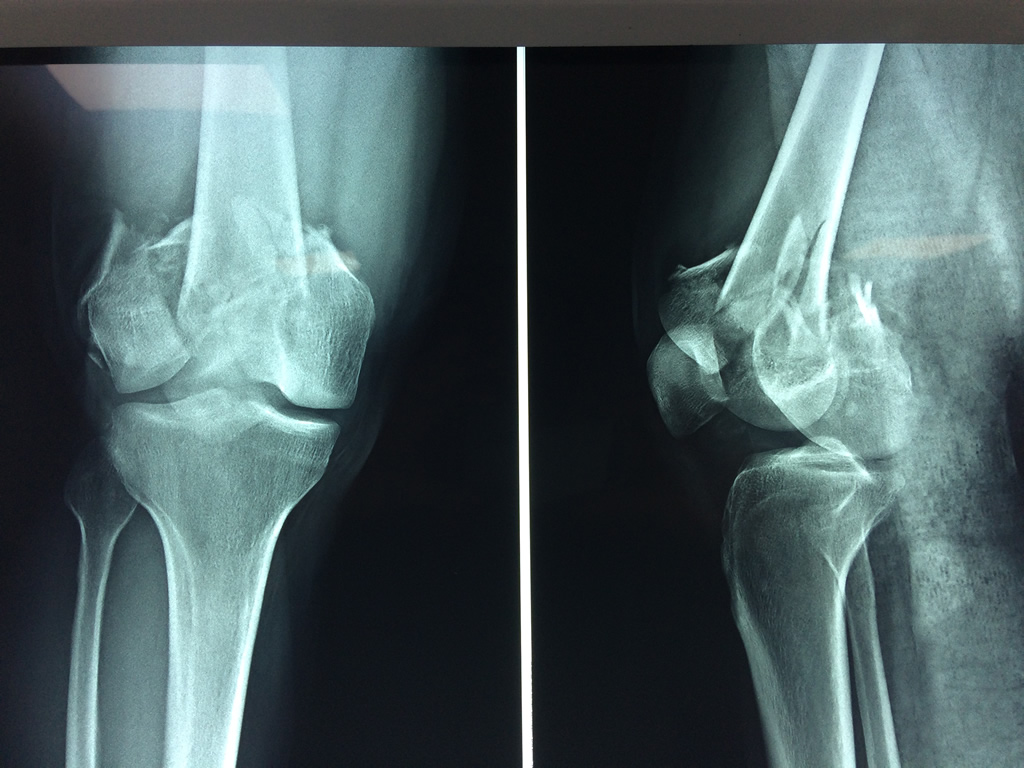

Cirugía de Cadera

El fémur es el hueso del muslo, el segundo segmento del miembro inferior. Es el hueso más largo, fuerte y voluminoso del cuerpo humano.